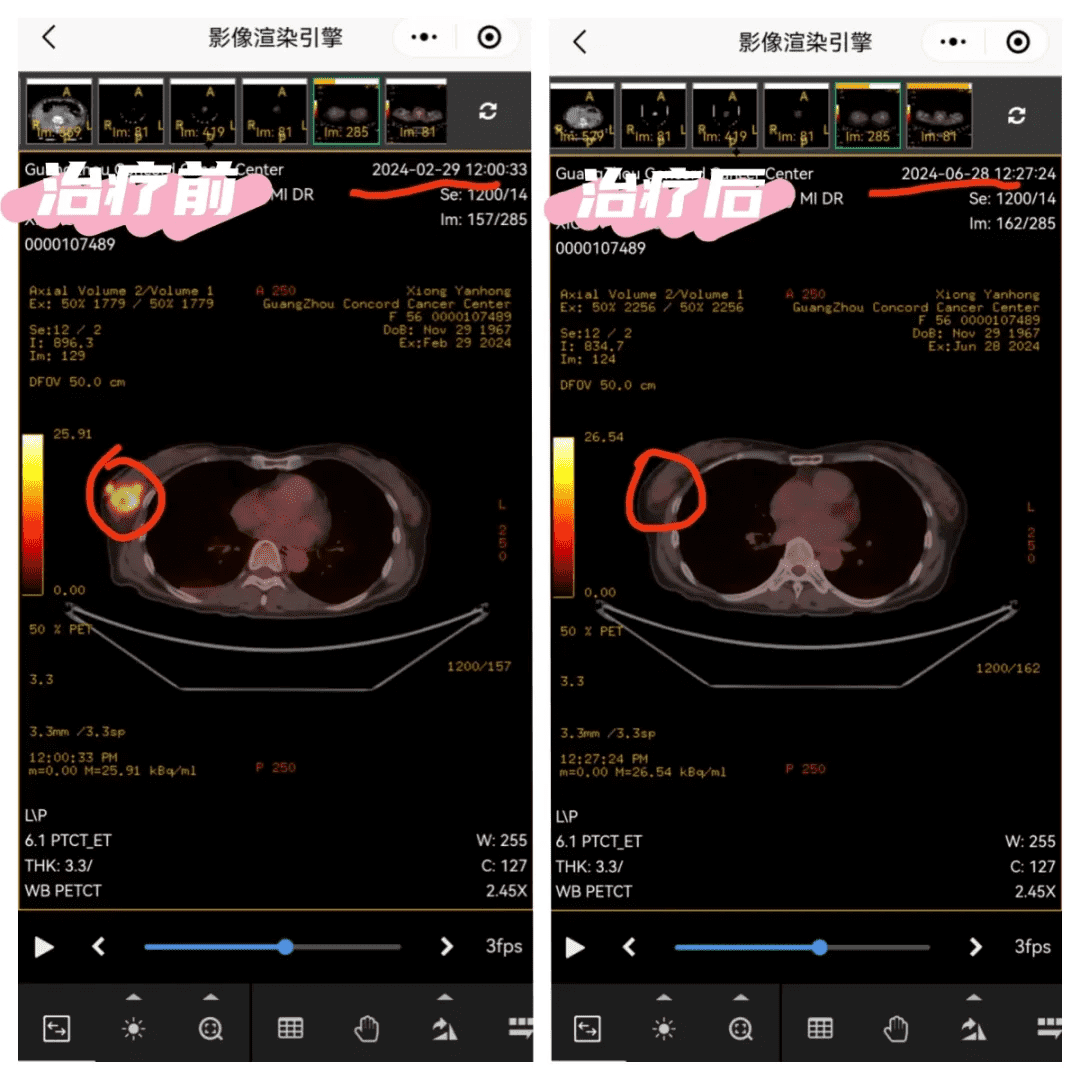

Comparison of imaging data at initial admission and after four courses of treatment:

The original high metabolic mass on the right breast disappeared

On February 28, Ms. Kang came to our hospital's minimally invasive interventional department for the first time. On February 29, PET/CT showed a mass in the right lower outer quadrant of the breast (size 4.0*3.7*2.8cm) with increased metabolism, suggesting right breast cancer.

A PET-CT scan on June 28th showed the following: 1. Following comprehensive treatment for right breast cancer, the hypermetabolic mass in the right breast had disappeared, with no signs of tumor activity in the right breast. The right axillary lymph nodes had significantly shrunk, with decreased metabolism, suggesting improvement after treatment of the metastatic tumor. 2. The previous "small bilateral pneumothoraces (right hydropneumothorax)" had resolved.

Comparison of the two examinations showed that in just four months, the tumor disappeared, the metastasis improved, and the bone metastasis metabolism decreased.